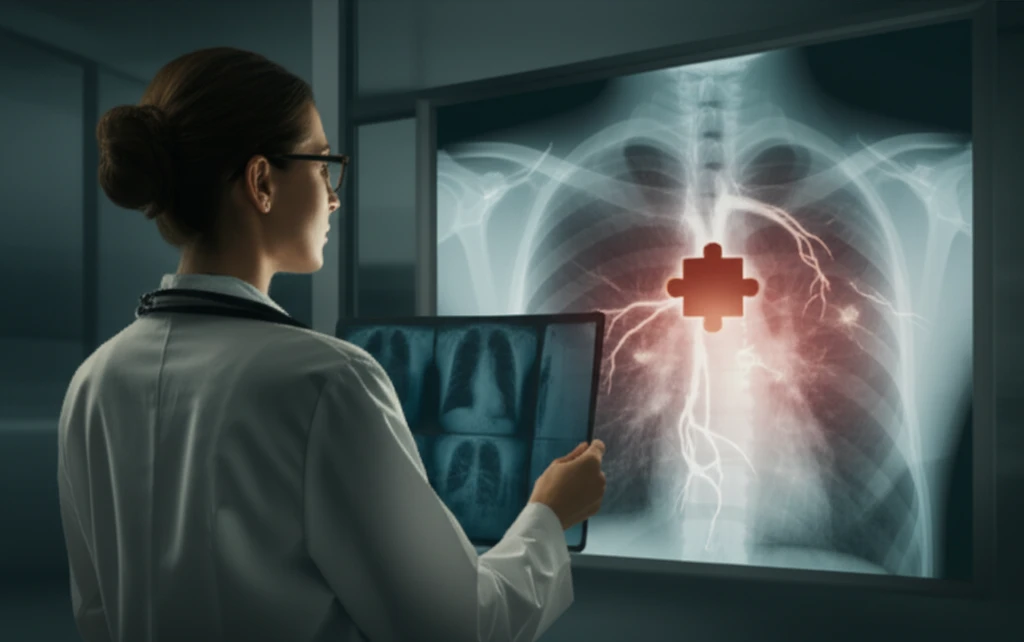

Mediastinal tumors, or growths in the chest area between your lungs, are often discovered by chance during routine check-ups or scans for something else. While many are benign, figuring out exactly what they are can be tricky for doctors. Benign mediastinal lesions pose a significant diagnostic challenge to radiologists and pathologists.

These growths often have patterns that hint at certain conditions, but certainty can be elusive. When doctors can't be sure, surgeons may need to perform a biopsy during surgery to get a diagnosis and decide on the best course of action. This is where understanding rare conditions like Castleman disease becomes critical.

This article explores a case of Castleman disease, highlighting why it should always be considered when evaluating mediastinal tumors. By understanding this condition, we can improve diagnostic accuracy and patient care.